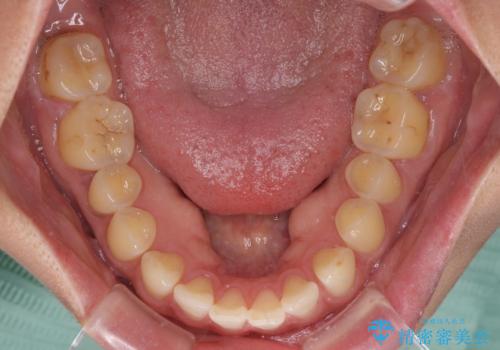

- 上顎前歯の隙間と口元の突出感を気にして来院された患者様です。

高校生の時に行った矯正治療の後戻りであり、歯列不正は軽度であったので、インビザラインにて治療を行うこととしました。

すきっ歯はあっという間に後戻りを起こすので、可及的に後戻りを防止するために、上下前歯部を舌側からワイヤーで固定しています。

通常は下顎前歯のみに行っていますが、空隙歯列弓では上顎でも行っています。